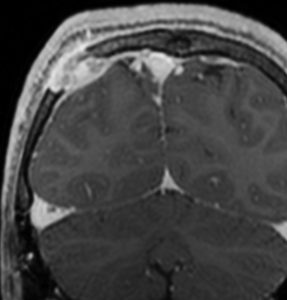

左はMRI T2強調画像です。まるで丸い腫瘍のように見えます。

下のT1強調画像では,ガドリニウム造影剤で強く増強されていて皮下に炎症性腫脹がみられ,活動期の病変であるのがわかります。

この病変は単発(孤発)病変ですが,ややいびつな形をしていて,頭皮の方に盛り上がっていますから,活動性の病変です。手術で完全摘出すると治りますから,骨欠損が広がるようなら手術したほうがいいです。理由は,手術が簡単なこと,病理診断がつくこと,これ以上の病変の広がりを抑えることです。最近は自然の骨に近いような人工骨で補填することができますが,骨形成しなくても自然修復で骨形成されます。とくに,低年齢児では骨形成をしない時もあります,頭蓋骨が自然再生するからです。